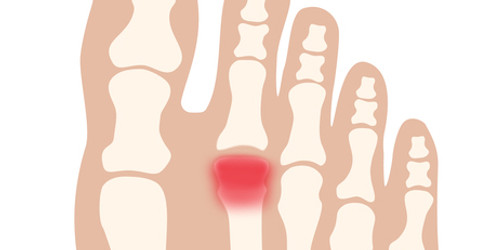

中足痛(症)/Metatarsalgia

中足痛/Metatarsalgia

​足趾の付け根部分に痛みや炎症が生じている状態です。ランニングやジャンプを伴う運動のほか、足の骨格の変形や合わない靴(きつすぎる、またはゆるすぎる靴)も原因になります。

中足痛(症)には、いくつかの日本語訳があり、「中足骨痛症」「中足骨頭部痛」「中足骨骨頭部痛」などと呼ばれることもありますが、日本足の外科学会の用語集では「中足痛(症)」とされています。